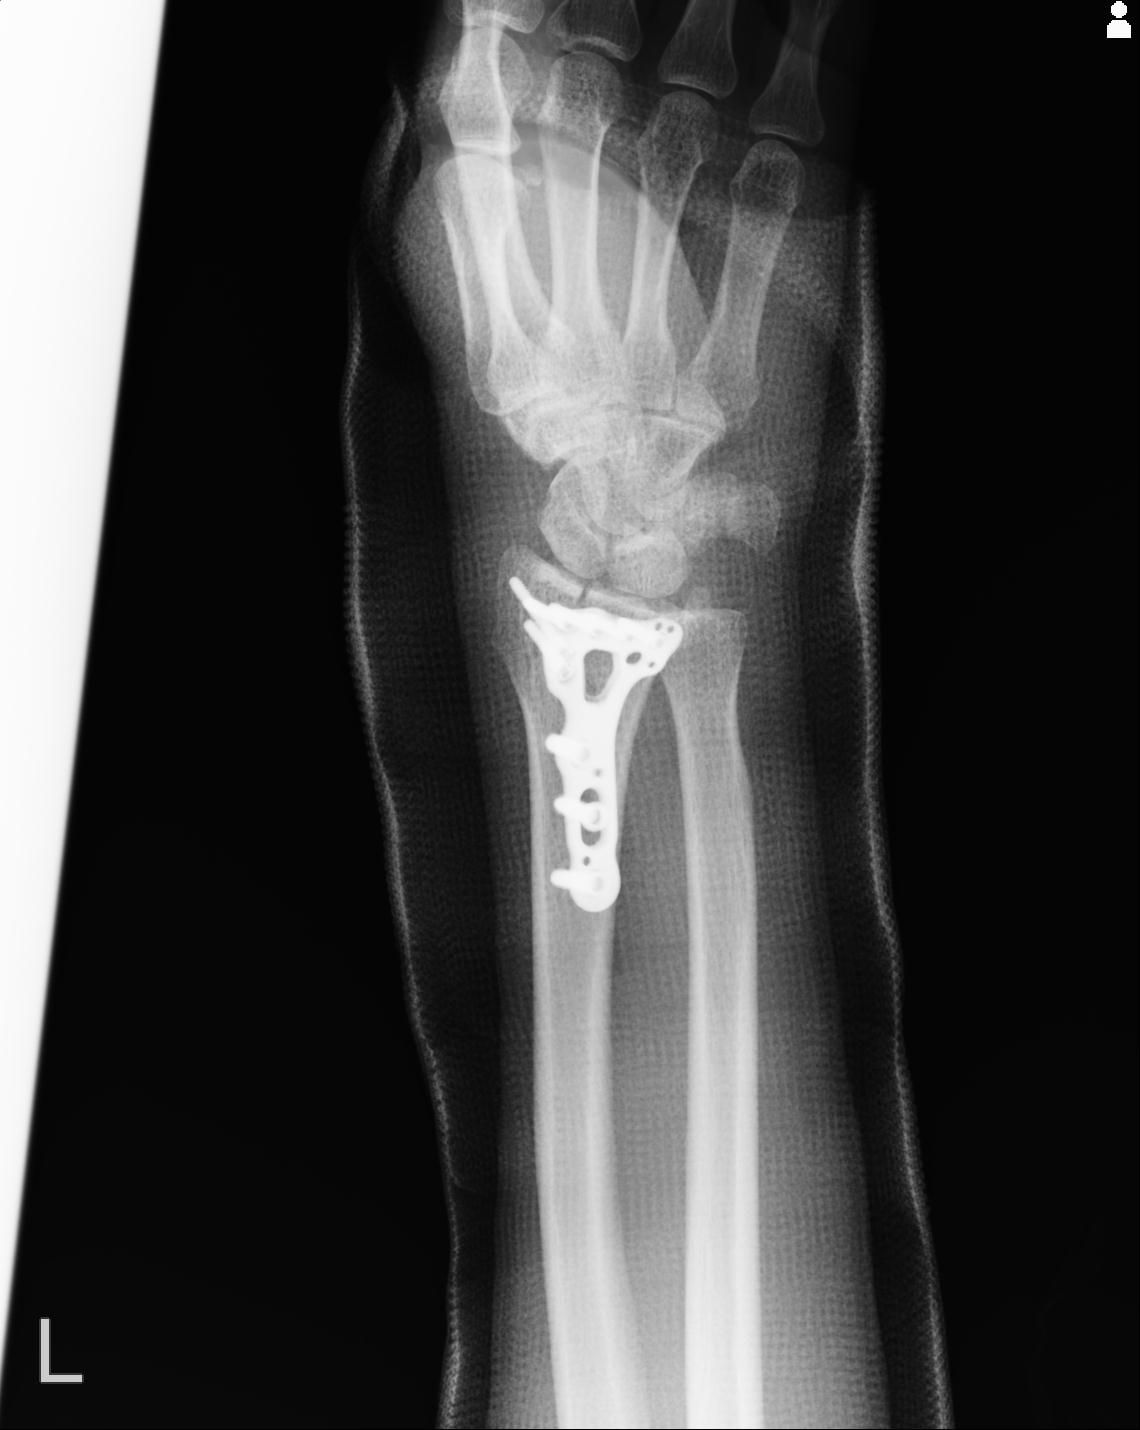

102766 1/5 1/12 左手関節 4R 28歳男性 左橈骨遠位端